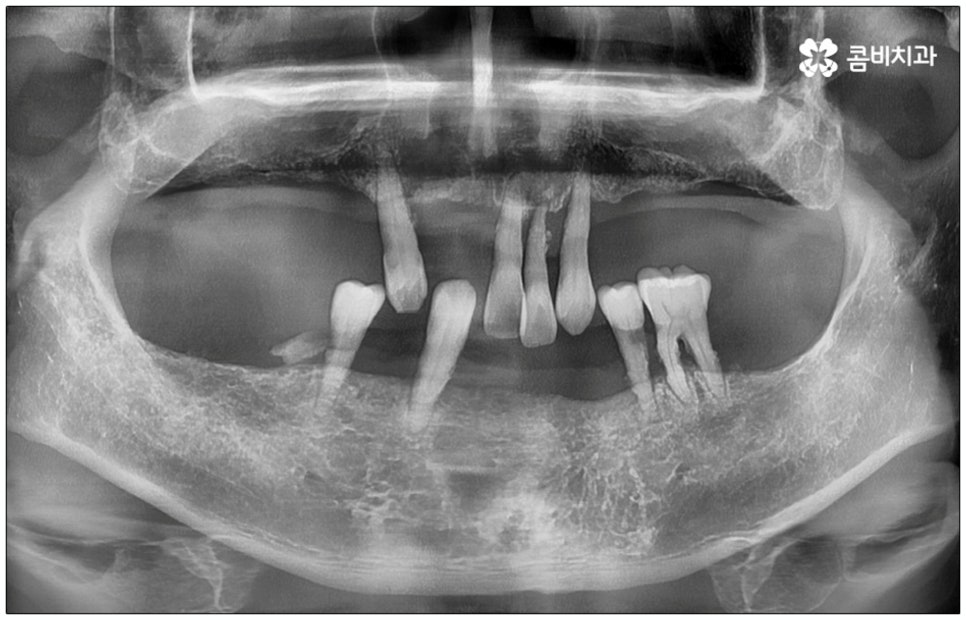

성인 이후 치아 상실의 주된 원인은 바로 풍치인데요, 풍치 즉 치주 질환은 잇몸(치은)을 포함한 치아 주위 조직에 급성 또는 만성으로 염증이 생겨서 손상이 일어난 것을 의미하고 있습니다. 이러한 풍치의 주된 원인은 치태와 치석으로, 음식물 찌꺼기와 치아 표면의 세균막(치태=플라그)이 엉겨붙어 굳어진 치석은 평상시의 칫솔질로는 제거되지 않기 때문에 스케일링 치료를 통해 주기적으로 제거해 줄 필요가 있어요. 치석이 점점 쌓이면 세균이 급증하는 온상이 되어 주변 조직에 염증이 발생하기 쉽고 병증이 심해질수록 치주인대와 치조골까지 손상이 깊어져 결국 치아가 빠지게 되는 거예요. 풍치로 치아를 잃게 되면 임플란트를 심는데도 어려움이 있기 때문에 이렇게 상황이 나빠지기 전에 제 때 적합한 치료를 받을 필요가 있어요. 하지만 잇몸의 경우 병증이 많이 깊어질 때까지 잘 알아차리기 힘든 경우가 많으므로 정기 검진 및 스케일링과 같은 평상시의 관리가 중요하다는 말씀을 드린 거예요.

특히 다수의 치아를 상실했을 때 전체적인 교합, 골조직 및 잇몸 상태, 얼굴형과의 조화 등 모든 부분을 종합적으로 고려하여야 하며 노인임플란트 수술의 경우 다양한 변수가 발생할 수 있기 때문에 이러한 고난도 임플란트 케이스에 노련하게 대처할 수 있도록 풍부한 임상 경험과 노하우를 갖춘 의료진인지, 정밀 검진 기계를 보유하고 있는지, 처음부터 끝까지 철저한 케어 시스템을 갖추고 사후 관리까지 꼼꼼하게 진행하는지 등을 잘 살펴보시고 임플란트 수술을 진행할 치과를 신중하게 선택하시길 권유드리고 있습니다.

특히 만 65세이상 부분 무치악 환자의 경우에는 노인임플란트 수술을 받을 때 건강 보험 혜택을 통해 평생 2개까지 자기 부담금 30%로 보다 저렴하게 이용해 볼 수 있으니 이에 대해서도 잘 알아보시고 도움받아 보시길 바라고 있어요. 만약 구강 질환이 너무 많이 진행되어 잇몸뼈가 이미 상당 부분 녹아서 뼈이식이 추가로 이루어져야 하거나 상악동 거상술과 같이 노인임플란트 수술의 안전성과 지속성을 높이기 위한 사전 처치가 필요한 경우 등에 있어서는 보험 혜택 대상에서 제외되는 부분이 있을 수 있으니 자세한 사항들은 의료진과 꼼꼼하게 상담해 보시고 진행해 보시면 좋을 거예요.